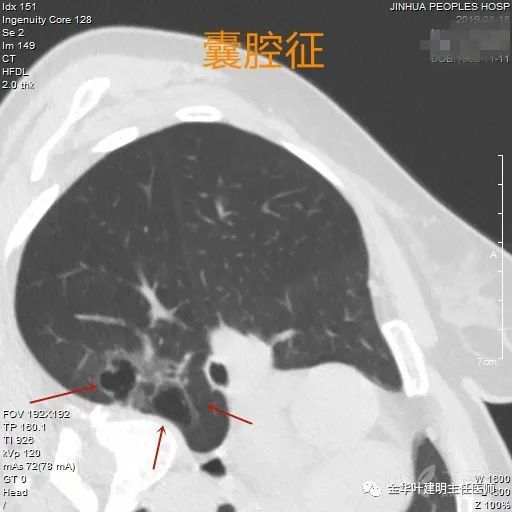

囊腔征

囊腔征:此征与空泡征的区别时,空腔部分体积较大,大于有形部分,以致容易误诊肺大泡。它虽然看着像大泡,但它的壁明显不正常,比肺大泡的厚,有磨玻璃成份,且往往不同方向厚薄不均。记住,这不是肺大泡,是囊腔型肺癌。